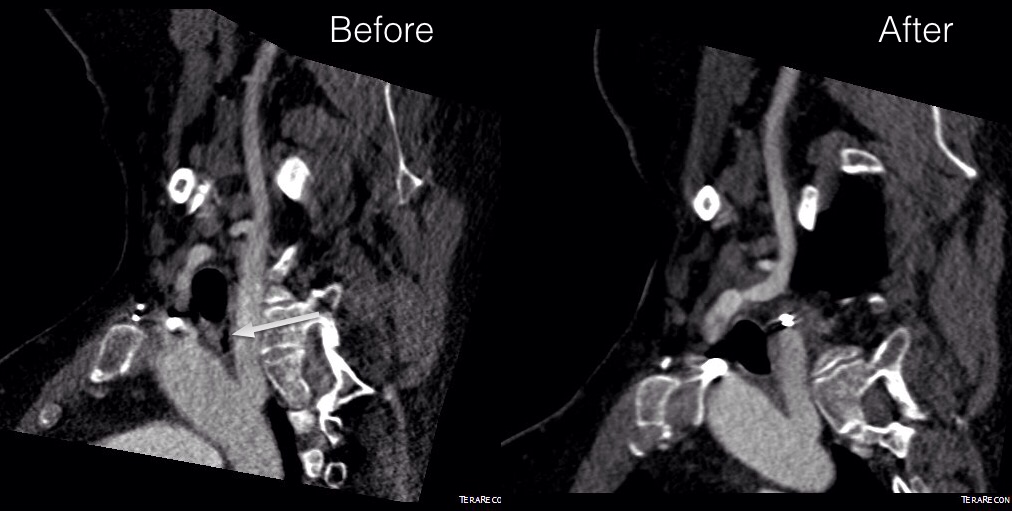

The EVAR was performed percutaneously. No endoleak was detected by completion arteriography (figure). He was soon discharged and was grateful. In followup, CT scan showed excellent coverage of the proximal and distal zones and absence of type III endoleaks. There was increased density to suggest a type II leak, but his inferior mesenteric artery was not the source of it. over a three year period, his aneurysm sac continued its 2-3mm of annual growth despite the presence of the the stent graft.

Three years of followup showed growth of the AAA sac to 5.5cm, which ironically threshold for repair. Again, no type I or III endoleak could be seen. He reached his calculated repair date, and I discussed our options in detail.

I waited a year before putting this together as I wanted CT followup. The sac stopped growing and has shrunk a bit back to 5cm or so. There will be those who argue that nothing needed to have been done about this leak as it would have stopped growing eventually, but I would counter that an aneurysm sac that kept growing like the stent graft never went in is one demanding attention. The key role of duplex ultrasound cannot be minimized. We have an excellent team of vascular scientists (their title in Europe), and postop duplex confirmed closure of the leak.